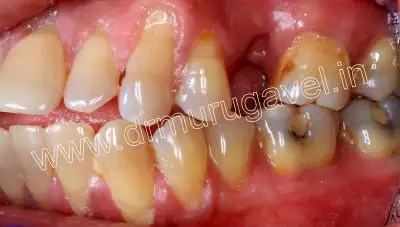

Initial presentation

Before treatment front view

pre-op upper occlusal view

pre-op side view